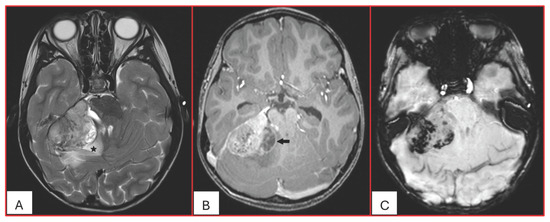

Since their first description by Rorke in 1995, the histogenesis of ATRTs has remained an enigma. Due to the expression of neural, epithelial, and mesenchymal markers, they likely derive from pluripotent fetal cells. Based on genetic and DNA methylation status and transcriptome profiles, ATRTs are further divided into three distinct molecular subgroups: ATRT-SHH, ATRT-TYR, and ATRT-MYC; further subclassifications have also been proposed. The WHO Classification of CNS tumors has included ATRTs in “Embryonal Tumors”. ATRTs are distinct from other embryonal tumors in their clinical presentation, tumor location, imaging characteristics, and prognosis. ATRTs often represent a surgical challenge as treatment requires removing a deep-seated large vascular mass from young patients. They are often resistant to conventional chemotherapy. Radiation therapy, which is imperative, raises serious concerns with regard to effects on the developing CNS of young patients. Safe and effective therapeutic measures are urgently needed.